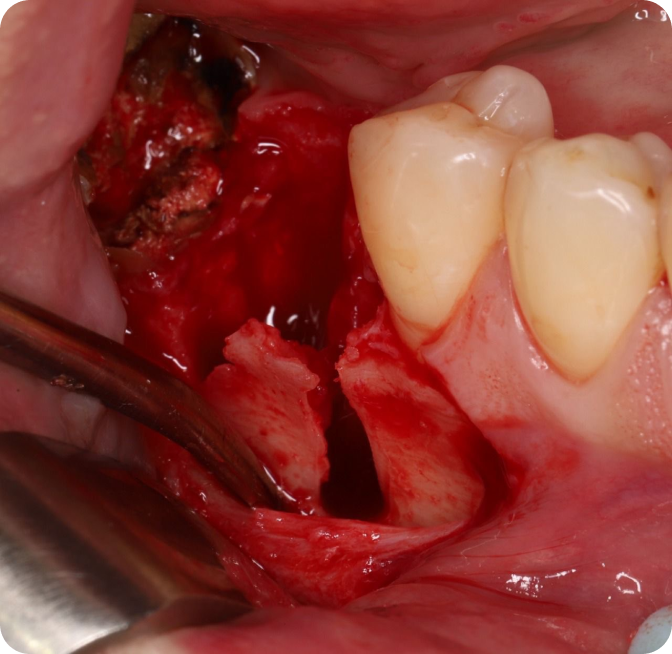

Методика удаления зубов в боковом сегменте нижней челюсти

Что будет в модуле:

Атравматичное удаление премоляров и моляров нижней челюсти

Инструменты и пошаговые алгоритмы удаления

План действий, если на вершине корня моляра имеется гиперцементоз

На демонстрациях операций вы получите точные протоколы работы в боковом сегменте нижней челюсти и научитесь работать в условиях гиперцементоза.